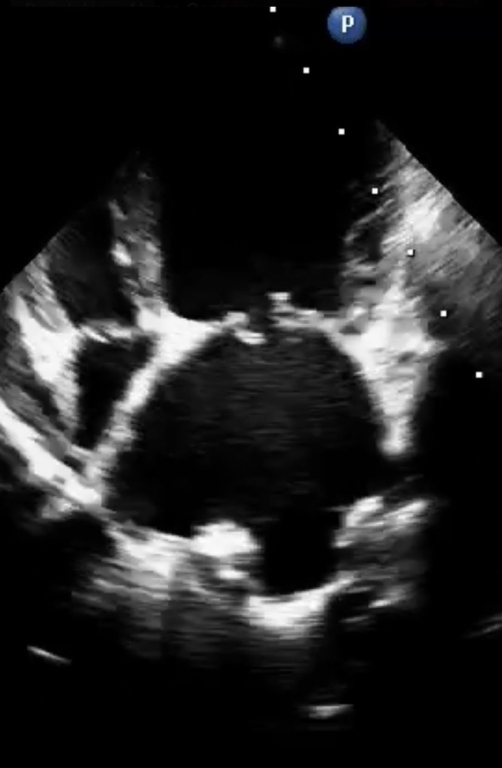

With thanks to Pablo Donati

MMVD is a common cardiac disease in dogs and can be present in any breed, though is particularly seen in some small breeds such as the Cavalier King Charles Spaniel and Dachshund. This study, from researchers in Argentina, Italy, Austria and Chile, set out to evaluate the efficacy of and adverse events from the administration of ACEIs to treat preclinical MMVD in dogs, via a systematic review of published evidence conducted according to the Cochrane Handbook for Systematic Reviews of Interventions. Certainty of evidence was assessed using the GRADE (https://gradepro.org) approach. The main finding in relation to dogs with preclinical MMVD and cardiomegaly was backed by a high certainty of evidence. The certainty of evidence in relation to the efficacy of ACEI administration in dogs without cardiomegaly was low.